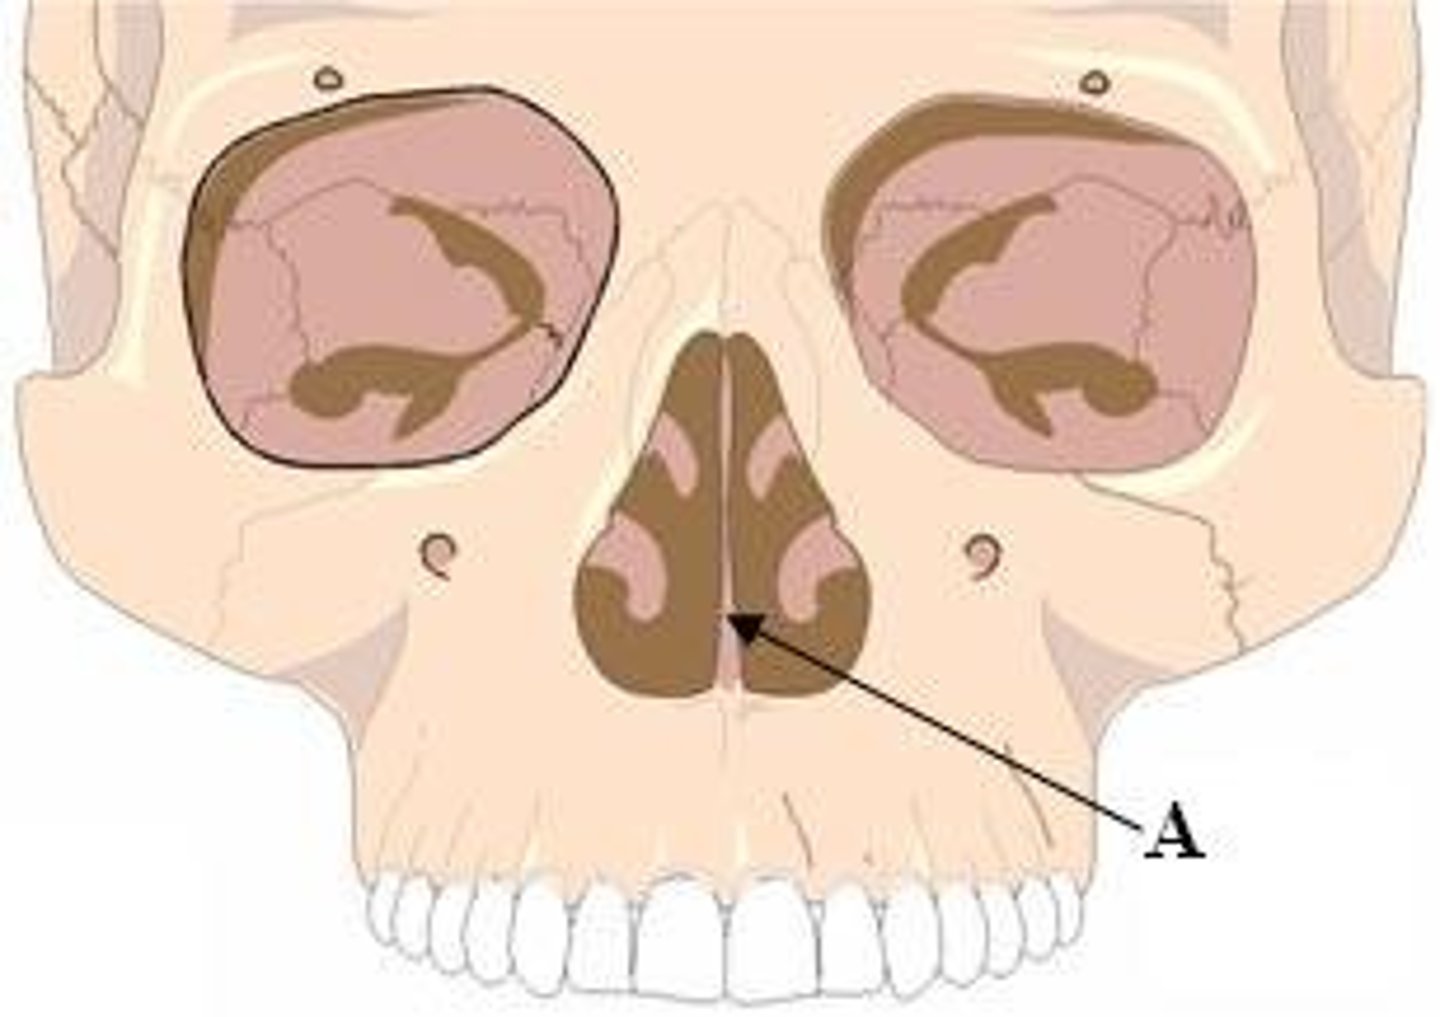

nasal septum

knowt flashcard image

nasal cavity